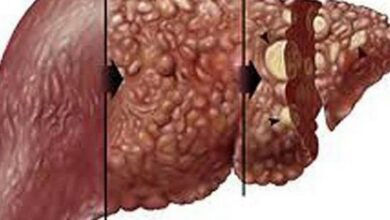

يُحطّم الكبد أغلب الكحول الذي يتناوله الإنسان، ولكن ينجم عن تحطيم جزيئات الكحول مركبات ضارة تُلحق الأذى بخلايا الكبد، وتُضعف المناعة عامة، وتُسبب الالتهابات، وحقيقة يتناسب الضرر الذي يلحق بالكبد تناسبًا طرديًا مع كمية الكحول المتناولة، والجدير بالبيان أنّ أولى مراحل أمراض الكبد الكحولية ما يُعرف بمرض الكبد الدهني الكحولي (بالإنجليزية: Alcoholic fatty liver disease)، وأمّا المراحل اللاحقة فتتمثل بالتهاب الكبد الكحوليّ وتشمّعه (بالإنجليزية: Cirrhosis)، وأمّا بالنسبة لعلاج أمراض الكبد الكحولية فتعتمد على مرحلتها؛ فمثلًا يعتمد علاج المرحلة الأولى (مرض الكبد الدهني الكحوليّ) على الامتناع التامّ عن شرب الكحول، ويمكن طلب المساعدة الطبية في ذلك، وقد يلجأ المختص لوصف أدوية تُقلل اشتهاء الكحول أو حتى تُسبب المرض للجسم في حال شربها، وأمّا بالنسبة لتشمع الكبد فيمكن السيطرة على المشاكل التي يُسببها بوصف أدوية معينة، ولكن إذا وصل الأمر إلى مرحلة الفشل الكبديّ؛ فإنّ زراعة الكبد (بالإنجليزية: Liver Transplant) هي الحل الوحيد لعلاج المشكلة.[٤]